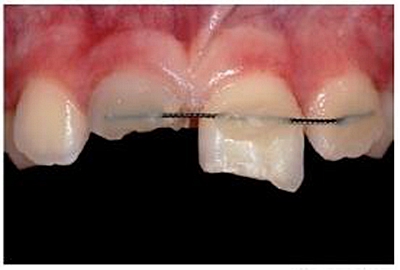

專業(yè)醫(yī)師對患者進行了仔細檢查及診斷分析。11被診斷為冠根折伴牙髓暴露及大面積牙體缺損。21被診斷為側(cè)向移位伴冠折。檢查活動夾板在位,兩中切牙根管治療術中,氫氧化鈣根管內(nèi)封藥。11明顯變色。11用Cavit暫封,21復合樹脂充填。11腭側(cè)頸部有一折裂片。

牙本質(zhì)和牙釉質(zhì)經(jīng)過全酸蝕(酸蝕劑)后,涂布粘接劑(Syntac; Ivoclar Vivadent),準備樹脂修復。利用已完成的硅膠導板輔助修復體的腭側(cè)成型(圖13)。牙本質(zhì)核采用不同顏色、不透光的牙本質(zhì)樹脂分層連續(xù)堆積

切端則采用透明樹脂,最后使用釉質(zhì)樹脂(Amaris, VOCO, Cuxhaven, Germany)。21的樹脂修復采用類似的方式。修復初步成型,拋光,恢復干燥牙釉質(zhì)的顏色。攝片顯示樁在根管內(nèi)位置合適(圖15)。最后一次復診精修、拋光充填體,完成治療。